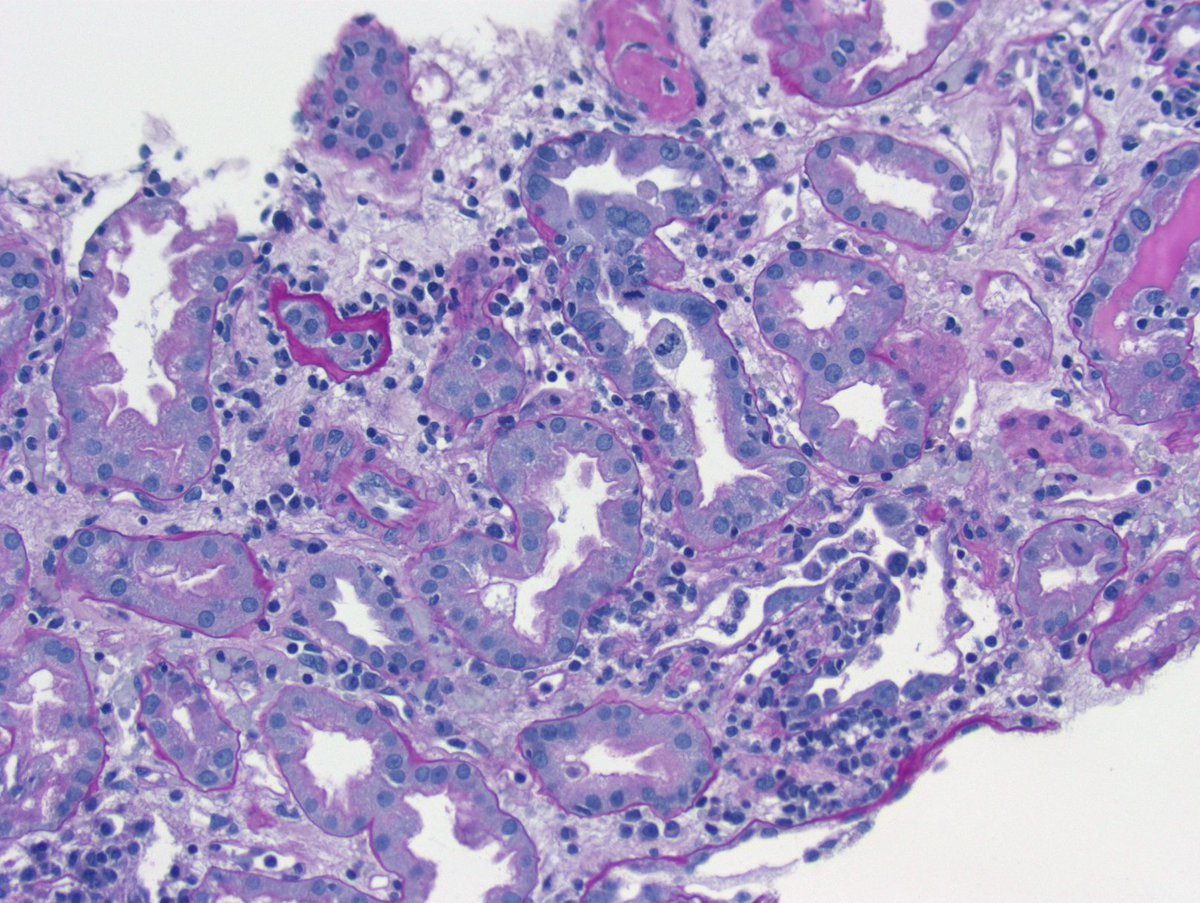

Long weekend often brings urgent cases. Here is one that was STATed, ended up showing anti-GBM GN. Diffuse crescents (nearly 100%). Linear IgG. #RenalPath